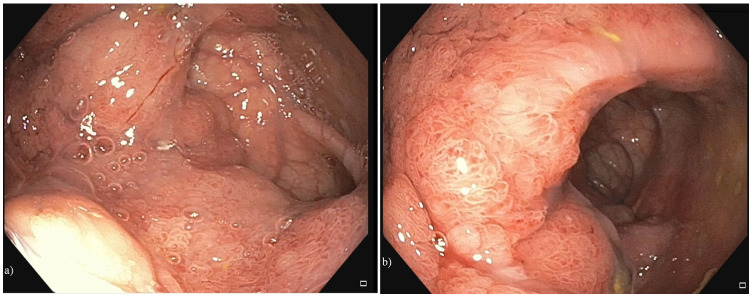

病例介绍:一名67岁男性,在数周的呕吐、虚弱和反复的晕厥发作后出现短暂的意识丧失和头晕。初步实验室结果显示低钠血症(Na 125 mEq/L)、严重低钾血症(K 2.3 mEq/L)、低氯血症(Cl 77 mEq/L)、代谢性碱血症(pH 7.5; HCO3- 34 mEq/L)、低血清渗透压(263 mOsm/L)伴尿浓度不适当(332 mOsm/kg)和肾前氮血症(肌酐3.4 mg/dL; eGFR 19 mL/min/1.73 m2;血尿素209 mg/dL)。CT增强及结肠镜检查发现直肠上部有一个大的粘液分泌绒毛状腺瘤。补充液体和电解质后,患者接受手术切除,症状完全缓解,并在随访中纠正了电解质异常。结论:直肠绒毛腺瘤应考虑在老年人不明原因的低血容量,低钾性低钠血症和代谢性碱血症。早期识别和明确切除是治疗和预防肾损伤的有效方法。

Case Presentation: A 67-year-old man presented with transient loss of consciousness and dizziness after weeks of vomiting, weakness, and recurrent syncopal episodes. Initial laboratory findings showed hyponatremia (Na 125 mEq/L), severe hypokalemia (K 2.3 mEq/L), hypochloremia (Cl 77 mEq/L), metabolic alkalemia (pH 7.5; HCO3- 34 mEq/L), low serum osmolality (263 mOsm/L) with inappropriately concentrated urine (332 mOsm/kg), and prerenal azotemia (creatinine 3.4 mg/dL; eGFR 19 mL/min/1.73 m2; blood urea 209 mg/dL). Contrast-enhanced CT, along with colonoscopy, identified a large mucus-secreting villous adenoma in the upper rectum. After fluid and electrolyte replacement, the patient underwent surgical resection with complete remission of symptoms and correction of electrolyte abnormalities on follow-up. Conclusion: Rectal villous adenomas should be considered in older adults with unexplained hypovolemia, hypokalemic hyponatremia, and metabolic alkalemia. Early recognition and definitive resection are curative and prevent kidney injury.